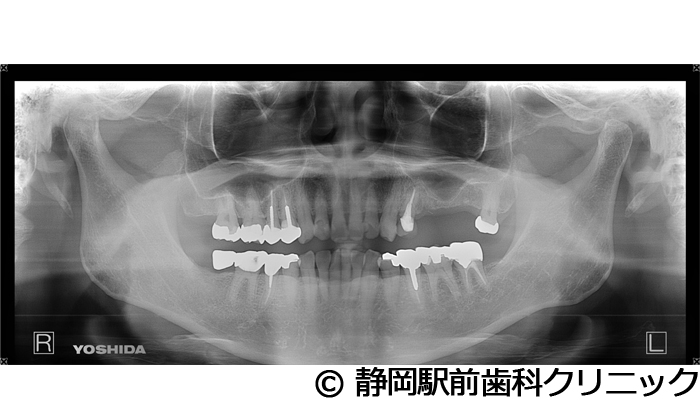

【症例5】全顎的インプラントとセラミックによる審美補綴

- 治療前

- 治療後

- 治療名

- 全顎的インプラントとセラミックによる審美補綴

- 費用

- 1,800,000円(税込)

- 期間

- 1年6ヵ月

治療内容

患者様の症状

-

全体的に歯がないため、噛めない。インプラント治療希望。

治療方法

全体的に残根は抜歯を行い、術前にCTを撮影し緻密に治療計画を立てた。インプラント埋入はブロックごとに行い、噛み合わせの調整を重ねた後、人工歯を被せて咬合と審美の回復を行いました。

治療結果

しっかり奥歯で食べ物を噛み切ることができるようになり、何でも食べることができるようになったと喜んでいただくことができました。口元を気にせずに笑うこともできるようになり、見た目もキレイになったとご満足いただけました。

※治療結果は個人差があります。

治療を行う上での注意点(リスク・副作用)

術後は、出血、腫れ、痛みなどが出る可能性があります。